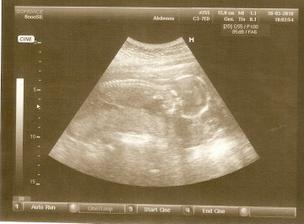

Budeme 3!

28/12/09 jsem poprvé našla slabounké čárky na testíku

12/1/10 jsem objednaná k paní doktorce, snad bude všechno v pořádku